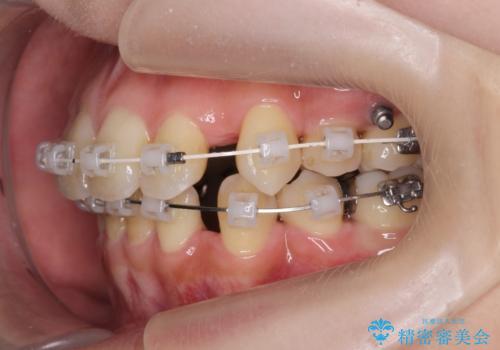

- ワイヤー矯正

- 治療期間

- 3年

全部の歯が入り切るスペースがなかったため、小臼歯4本を抜去しワイヤーを用いたマルチブラケット矯正を選択しました。